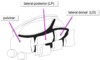

What is the medialmost layer?

What is the lateral most layer?

Medialmost- midline nuclei

lateral most-reticular nuclei

What bifuricates the thalamus into mrdial and lateral groups?

and what is the bifurication anterioly?

A sheet of myelinated fibers obliquely bisects the thalamus into ~ medial and lateral groups (= internal medullary lamina )

Anteriorly, the lamina bifurcates around the anterior nucleus